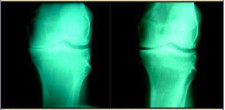

The Center for Regenerative Medicine (CRM) is paving the way with state-of-the-art, non-surgical treatments to help patients regain quality of life. In order to educate the public about all the non-surgical solutions, CRM created The Knee Diaries. Here is an excerpt from The Knee Diaries: "Patient is a 61-year-old male with the chief complaint of knee pain who visited The Center for Regenerative Medicine. He was diagnosed with bone-on-bone osteoarthritis of the left knee, causing him much pain and discomfort. He was informed that only a total knee replacement could help him. He is otherwise healthy. On exam, he had point tenderness to the medial side of the left knee (medical lingo: inner side). An X-ray showed severe arthritis of the knee (X-ray on the left). Patient started receiving treatments at The Center for Regenerative Medicine. Today, he is feeling much better (X-ray on the right).